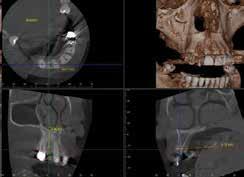

Cone Beam Computed Tomography

The foundational technology that makes a digital workflow possible in implant dentistry is cone beam computed tomography (CBCT). CBCT uses a single, inexpensive, flat-panel or image intensifier radiation detector. CBCT imaging is performed using a rotating platform to which the X-ray source and detector are fixed. The X-ray source and detector rotate around the object being scanned and multiple, sequential, planar projection images are acquired in an arc of 180 degrees or greater.6

X-ray attenuation measurements from each machine position are then used to reconstruct a 3D dataset of the implant site, which can then be used by CBCT viewing software to display either a 3D rendering or any cross-sectional view of the implant site.7,8 CBCT differs from computed tomography (CT)

in that it uses a single X-ray source that produces a cone beam of radiation, rather than a fan beam as with CT. There is no accepted definition of when a fan beam (which is assumed to be planar) becomes a cone beam.9

The significantly lower cost and smaller computing power needed to analyze CBCT images compared to computed tomography made this technology accessible to the dental practice in 1999, when the first commercially available CBCT machine, the NewTom DVT 9000, was introduced in Europe.8

The American Academy of Oral and Maxillofacial Radiology (AAOMR) recommends that cross-sectional imaging be used for the assessment of all dental implant sites and that CBCT is the imaging method of choice for this information. 8 Once a CBCT image is taken, it is recommended that the image be interpreted by an oral and maxillofacial radiologist. The AAOMR noted that “dentists using CBCT should be held to the same standards as board certified oral and maxillofacial radiologists (OMFRs), just as dentists excising oral and maxillofacial lesions are held to the same standards as oral and maxillofacial surgeons. It is the responsibility of the practitioner obtaining the CBCT images to interpret the findings of the examination. Just as a pathology report accompanies a biopsy, an imaging report must accompany a CBCT scan.”10

Merging the CBCT and Intraoral Scan Data

Once the CBCT DICOM and intraoral scan STL files have been created, they can be imported into the implant planning software. Many different implant planning software packages are available. Common examples are Planmeca Romexis, 3D Diagnostics 3DDX, 3Shape Implant Studio, Dentsply Sirona Simplant and BlueSkyPlan by Blue Sky Bio. Implant planning software have similar capabilities; the choice depends on the subscription model and the ease with which the software integrates into the existing hardware of a particular office. The images in this section are from BlueSkyPlan by Blue Sky Bio.

Fig. 1A Fig. 1B Fig. 2 Fig. 3A

The first step is to align the DICOM data containing bone and tooth surfaces with the STL data containing tooth and soft tissue surfaces. Some software merge the two datasets automatically. Additional manual refinement can be done by shifting the model in any of three axes to better align with the CBCT image. Aligning CBCT and tooth surface data can result in higher accuracy of implant placement. 18 If the software does not align automatically, you can manually do so by merging with points (Fig. 2). In this method, the software user must select a series of corresponding points on the model and the CBCT image, such as grooves or cusp tips, which are easily identifiable in both data sets. The software will then align the two datasets together based on the points selected.

Regardless of the alignment method, the accuracy of the alignment needs to be verified. If the models are well aligned, tooth surfaces from both the model and the CBCT should be intimately adapted on individual CBCT slices (Figs. 3).